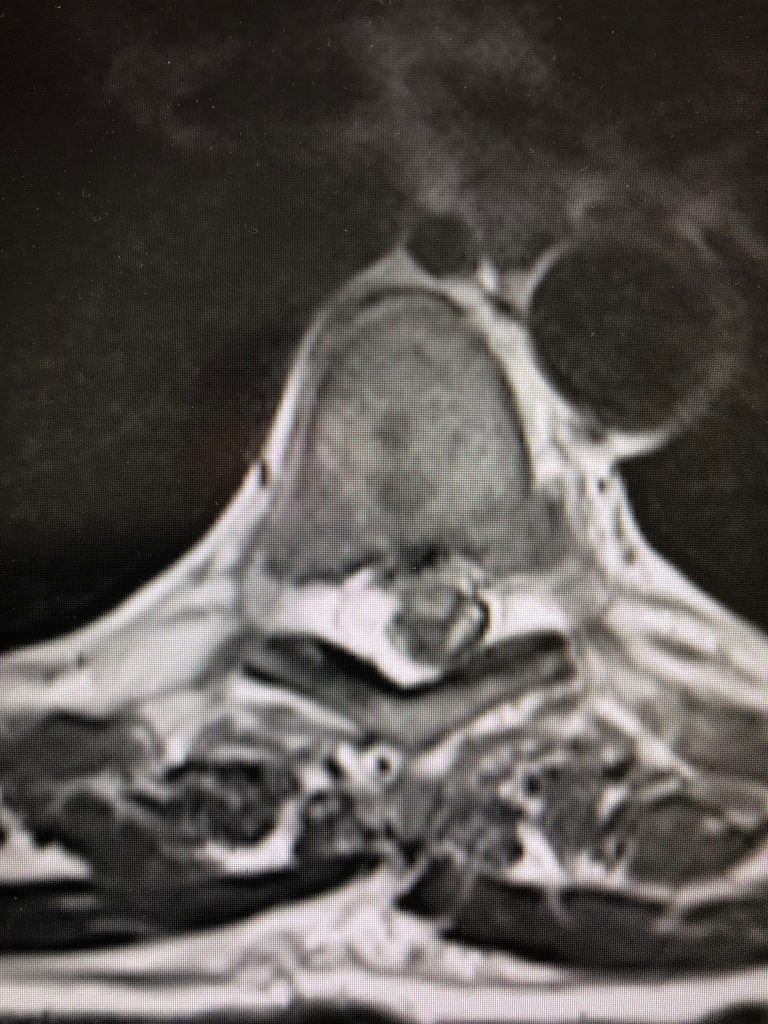

Ο απεικονιστικός έλεγχος ανέδειξε δύο επασβεστωμένες θωρακικές δισκοκήλες στο ύψος Θ6/7 και Θ7/8.

Οι θωρακικές δισκοκήλες, ειδικά όταν είναι επασβεστωμένες, αποτελούν χειρουργική πρόκληση, μια και η δισκοκήλη είναι σε άμεση επαφή με το νωτιαίο μυελό, ενώ στην προσπέλαση είναι σημαντικό να διαφυλαχθούν σημαντικές δομές όπως τα μεγάλα αγγεία του θώρακα, ο πνέυμονας κλπ.